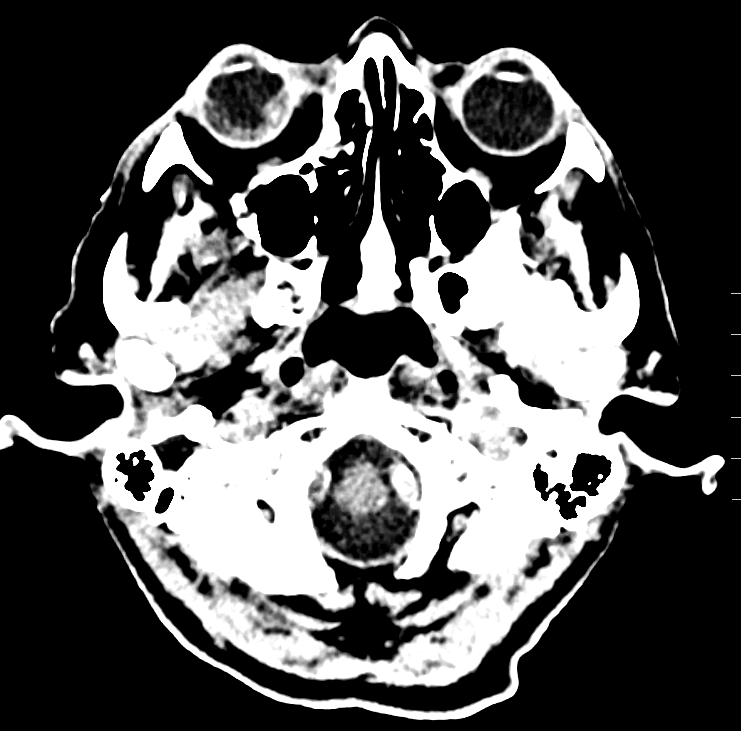

A dramatic head CT in a patient with monocular vision loss.

An elderly woman presented to the ER with complaints of sudden right sided headache and monocular right eye vision loss. Her blood pressure on presentation was 240/110 mmHg. Her non-enhanced head CT is shown.

In this case, the patient had a retinal hemorrhage in the right eye.